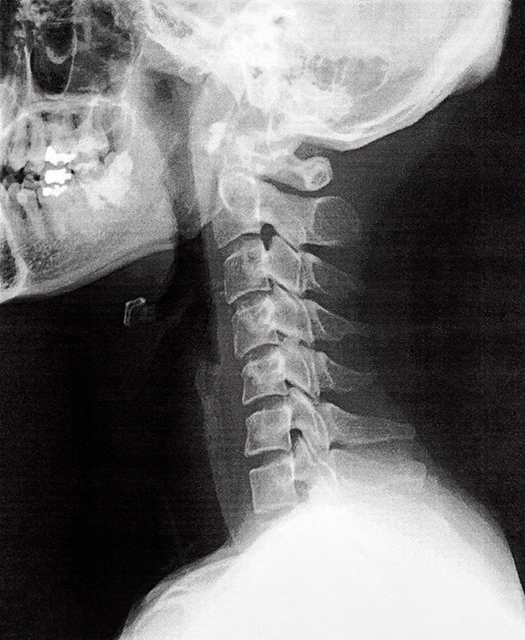

ストレートネック

デスクワーク、携帯やパソコンの見過ぎなどによって猫背になり頸椎に異常をきたします。頸椎は正常では湾曲していますが猫背により頸椎が伸展(ストレートネック)して異常になり約5㎏以上の頭を四六時中、首で支えることになり首の筋肉は緊張し固くなります。

頸椎は正常であれば湾曲していますが猫背の姿勢が長時間になると頸椎がストレートネック傾向になり首の筋肉がこり頭痛の原因になります。